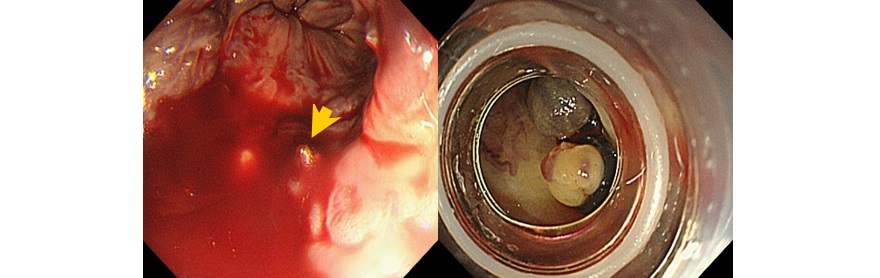

大腸ポリープ切除術、早期癌に対する内視鏡的粘膜剥離術、胃潰瘍などからの出血に対する内視鏡的止血術、食道静脈瘤からの出血に対する結紮術、アニサキス(寄生虫)や薬パッケージの誤飲に対する異物摘出術など。また胆道・膵臓系では、内視鏡を用いた胆石除去や、胆道感染や癌に伴う黄疸に対する内視鏡的な減黄術(ステント留置術)など各種行っております。

『食道静脈瘤破裂に対する結紮止血術』